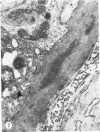

Immunopathologic findings in efferent ducts of 36 rhesus macaques vasectomized as many as 12 years earlier and of 11 age-matched control animals were compared. Electron-microscopic observation of these ducts revealed changes after vasectomy. The epithelium shortened from a prevasectomy height of 25 mu to 14 mu as the ducts stretched after vasectomy. The number of sperm and macrophages in the lumen increased. The basement membrane was 300-700 A wide in nonvasectomized animals but several times that in animals vasectomized 6 or more years before; the mean width significantly increased with time after vasectomy. Numerous electron-dense immune complexes were found within the thickened lamina in 33% of vasectomized animals and in none of the controls. The mean size of the electron-dense areas varied from 0.01 sq mu in a monkey vasectomized 3 years earlier to 0.18 sq mu in an animal vasectomized 7 years earlier; the mean area significantly increased with time after vasectomy. Frozen sections of testis and epididymis were evaluated through the use of fluorescein-conjugated antibodies. Of the nonvasectomized controls, 18% showed immune deposits. Of the vasectomized animals, 53% revealed C3 deposition in the basement membrane surrounding the efferent ducts. The presence of electron-dense deposits plus the finding of putative immune complexes as revealed by immunofluorescence suggested that vasectomy enhances leakage of sperm antigens, particularly in the region of the efferent duct.